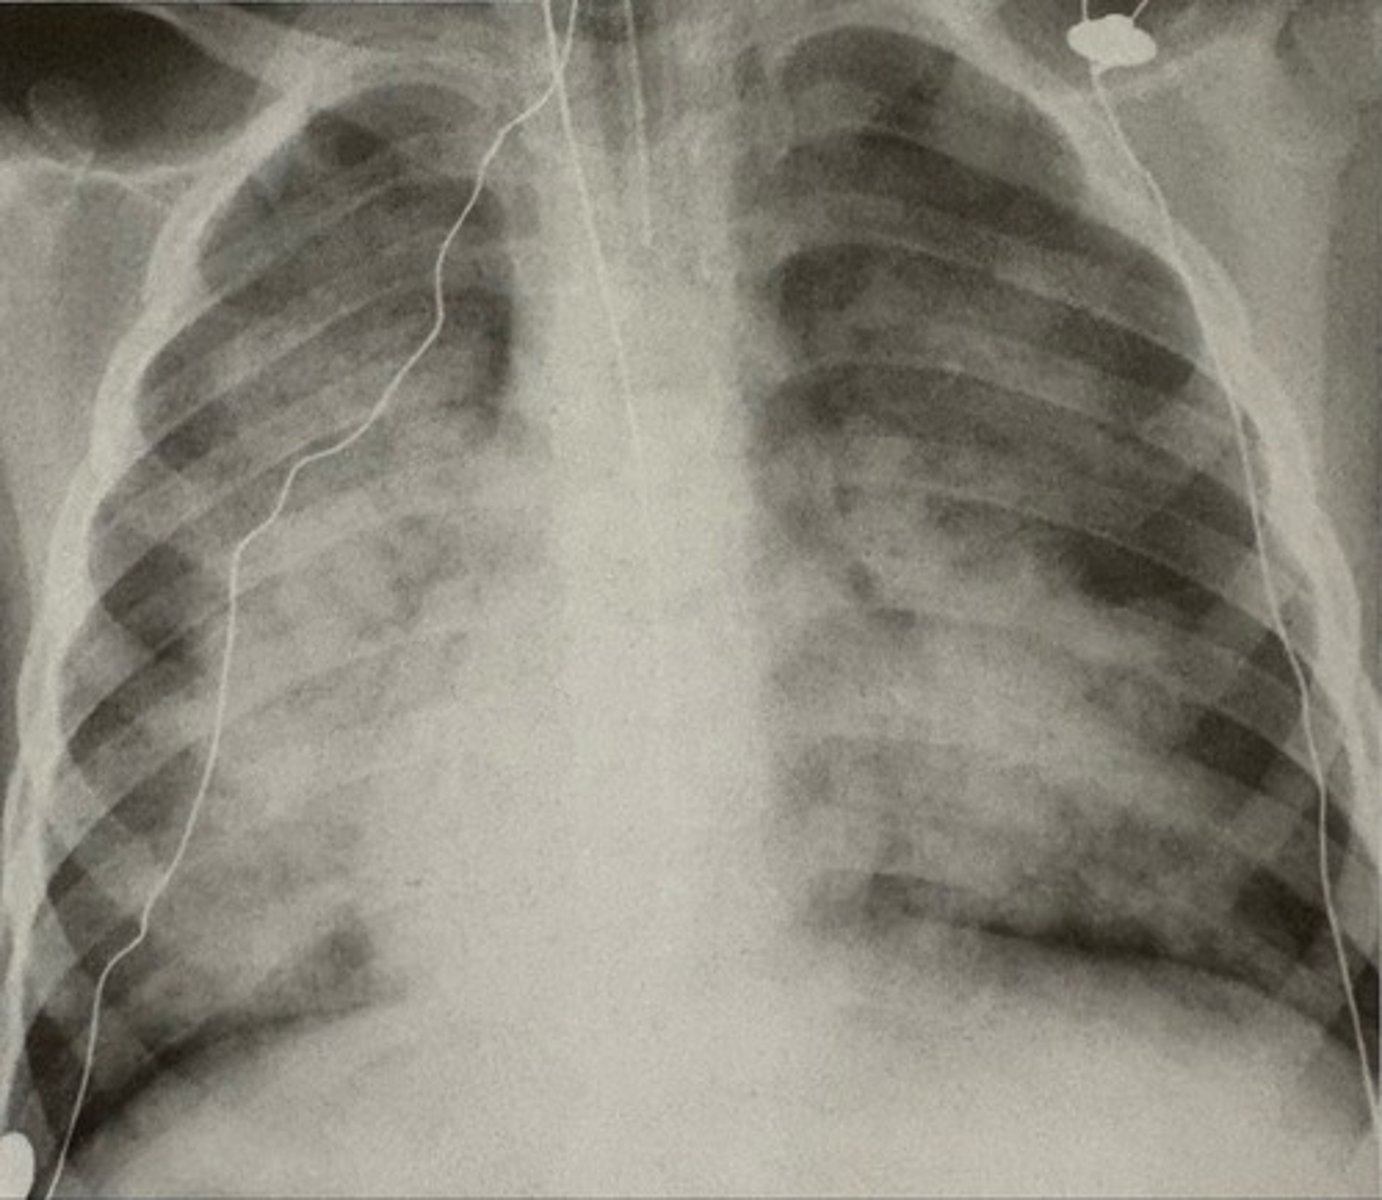

Eisenmenger Syndrome and atrial septal defect

what pathology is present?